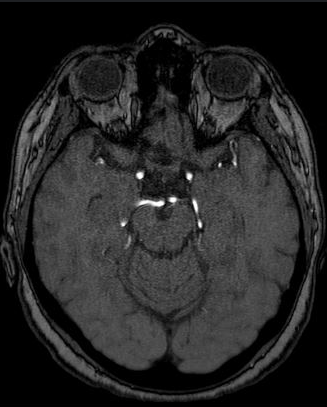

The selection of imaging modality significantly impacts the visualization of cerebrovascular structures, which is crucial for pre-operative neurosurgical planning. TOF-MRA relies on flow-related enhancement to effectively highlight large, fast-flowing arteries. However, as shown in Fig. 1 (a), TOF-MRA is limited in soft tissue contrast and often fails to adequately visualize small, slow-flowing vessels and venous structures. While its focused arterial visualization simplifies segmentation, it frequently results in incomplete vascular maps, particularly around tumor margins or in anatomically complex regions.

In contrast, T1CE MRI uses a gadolinium-based contrast agent to enhance areas of increased perfusion or disrupted blood-brain barriers, typically associated with neoplastic tissue. As depicted in Fig. 1(b), T1CE MRI provides superior soft-tissue contrast and enables visualization of both arteries and veins, including smaller vessels that are often missed by TOF-MRA. This detailed anatomical information is critical for surgical planning, particularly in understanding the tumor-vasculature interface.

Figure 1: Comparison of vascular and tissue visualization in TOF-MRA and T1CE MRI. (a) TOF-MRA highlights large, fast-flowing arteries with limited soft tissue contrast and poor visibility of small or slow-flow vessels. (b) T1CE MRI provides enhanced anatomical detail and visualizes both arteries and veins, including smaller vessels near pathological tissue, but introduces complexity in vessel segmentation due to nonspecific enhancement.